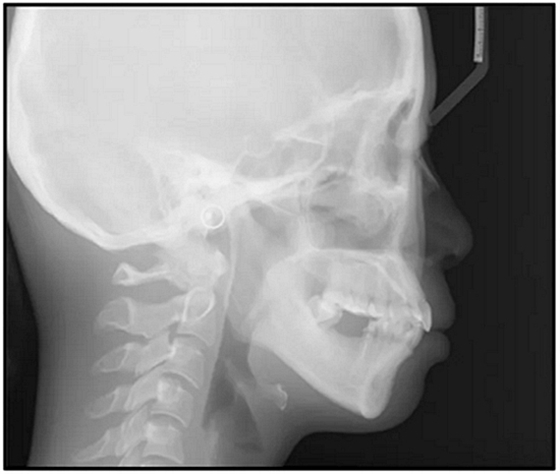

36歲;女性;尋求下頜左后方區(qū)域間隙管理的建議(圖1和圖2),通過(guò)治療獲得了良好的牙頜面效果(圖3和圖4)。她被診斷患有骨性I類和代償性牙性II類錯(cuò)合畸形,并且上頜左側(cè)尖牙缺失(圖1和2)。大約七年前,由于不可修復(fù)的齲齒,拔除了下頜左側(cè)第一和第二磨牙(圖5)。37相鄰的第三磨牙向近中移動(dòng)并傾斜入間隙,導(dǎo)致無(wú)牙頜間隙減小至約14 mm(圖2和圖5)。臨床和影像學(xué)評(píng)估顯示多發(fā)性齲損和在下頜右側(cè)567處有一不良的固定橋修復(fù)體(圖1和5)。此外,下頜左中切牙缺失,造成下頜中線向左側(cè)偏移約3 mm(圖1和圖2)?;颊咦栽V,她的右上第一前磨牙和左上尖牙在13歲時(shí)由其家庭牙醫(yī)拔除,因?yàn)樗鼈儽蛔枞筋a側(cè)萌出(圖1)。上頜第二磨牙缺失(未知病因),并且相鄰的第三磨牙已經(jīng)轉(zhuǎn)移到第二磨牙間隙中。如補(bǔ)充材料所示,美國(guó)正畸學(xué)差異指數(shù)DI是28分。種植體部位(下頜左側(cè)和右側(cè)第一磨牙)由于復(fù)雜性得到額外4分(補(bǔ)充材料)。

圖5. 治療前的側(cè)位片(上圖)和全景(下圖)的X光片